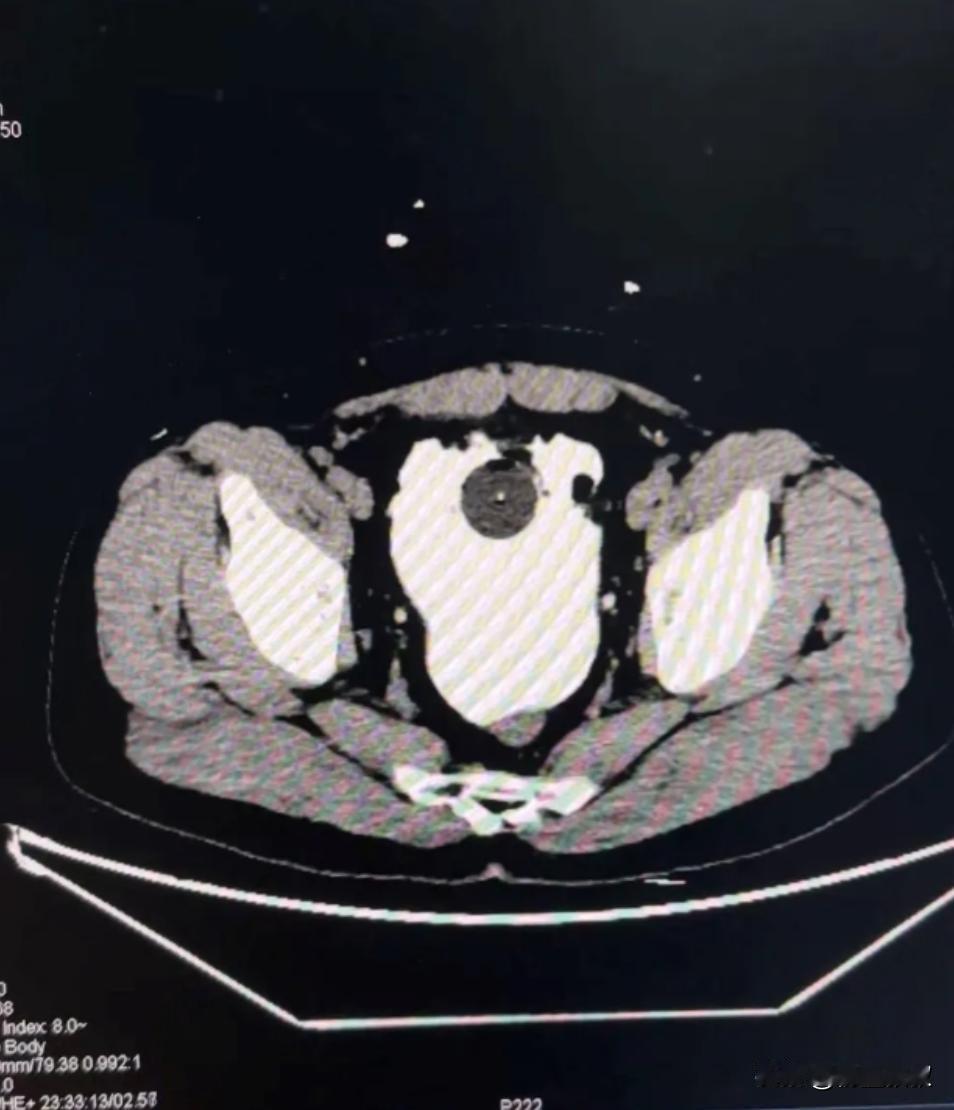

悲剧还是发生了!近日,陕西西安,一男子和朋友一起相聚喝酒,一连喝了8瓶啤酒下肚之后,却没有上过一次厕所,他正为此感到纳闷时,却发现自己上厕所居然怎么都尿不出来,到了医院检查才发现自己的膀胱已经破了一个6cm的大洞!网友:这也太能“憋”了。 前阵子陕西西安出了个事儿,听着挺日常的朋友聚会,最后却闹到要做手术,谁也没料到会这样,就是一个男的跟几个朋友凑一块儿喝酒,本来是想热热闹闹聚聚,结果几个人聊着天喝嗨了,他一不留神就喝了 8 瓶啤酒。 喝了这么多酒,按说正常人早该跑几趟厕所了,可他从开始喝到聚会结束,一次厕所都没去过,一开始他自己还没太在意,甚至有点纳闷心想怎么喝了这么多都没感觉,难道自己身体底子真这么好? 可等聚会散了,他琢磨着该去上厕所了才发现不对劲,不管怎么努力就是尿不出来,这时候他才开始慌,一开始还以为是喝多了反应慢,等了一会儿再试还是没用,肚子反而慢慢有点发紧,隐隐约约开始疼。 朋友看他脸色不对,问清楚情况后也急了,赶紧开车送他去医院,到了医院医生先问了情况,又安排做了检查,结果出来的时候,不光他自己,连陪着来的朋友都吓了一跳,他的膀胱破了个洞,而且还不小有 6 厘米长。 医生说啤酒本身就利尿,喝了 8 瓶身体里攒了不少尿,他一直憋着没排,膀胱就像个被撑到极限的气球,最后撑不住就破了,尿液漏到腹腔里,还引发了炎症,要是再晚来一会儿,情况可能更严重。 之后他就赶紧住院,做了紧急缝合手术,光手术就花了好几个小时,术后还得住院恢复,前前后后得小半个月才能好。 躺在病床上他自己也后悔得不行,说早知道这样,当时不管怎么都该去上厕所,哪儿能硬憋着,这一下不光自己遭罪,还得花医疗费,耽误工作太不值当了。 后来这事儿被网友知道了,大家也都议论纷纷,有人说 “这也太能‘憋’了,拿健康当玩笑”,还有人说自己也有过憋尿的情况,现在看了这个事儿以后再也不敢了。 可谁能想到,有时候就是这 “一会儿”,就可能把小问题憋成大麻烦,身体发出的信号可不能不当回事,不管是啥场合,健康永远是最重要的,可别再因为不好意思或者图方便,硬扛着憋尿了。 (信息来源:极目新闻——男子豪饮8瓶啤酒,尿意十足却仅有几滴排出,医生:膀胱撑出6cm巨大破口)